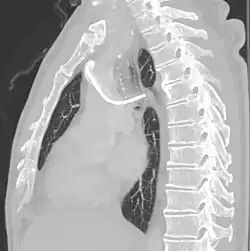

A port consists of a reservoir compartment (the portal) that has a silicone bubble for needle insertion (the septum), with an attached plastic tube (the catheter). The device is surgically inserted under the skin in the upper chest or in the arm and appears as a bump under the skin. It requires no special maintenance other than occasional flushing to keep clear. It is completely internal so swimming and bathing are not a problem. The catheter runs from the portal and is surgically inserted into a vein (usually the jugular vein or less optimally the subclavian vein). Ideally, the catheter terminates in the superior vena cava or the right atrium. This position allows infused agents to be spread throughout the body quickly and efficiently.

The port is then sutured on two sites to the underlying muscles. The tip of the catheter is checked for kinks and position using a fluoroscope. Besides that, aspiration of blood and contrast injection through the chemoport can also be used to confirm the position. The port is the closed in two layers (subcutaneous tissue is sutured first, followed by the skin). Sterile dressing is then placed on the port.[3] The optimum site to park the tip of the catheter is at the cavo-atrial junction or with margin of error of not more than 4 cm above the junction.[3]

The incidence of catheter fracture is 2.3%. The fracture can be due to "pinch-off syndrome" when the vein and the catheter is compressed when passes between the clavicle and first rib before turning 90 degrees into the superior vena cava. Fractured catheter component can dislodge most commonly into pulmonary arteries (35%), right atrium (27%), right ventricle (22%), and superior vena cava and peripheral veins (15.4%).[5]

Malpositioning of the catheter happens in 0.1 to 5.6% of the time. This can be due to malposition within or outside the superior vena cava. Causes includes: unexpected branches of the veins, vessel angulations, vein stenosis or venous tortousity.[5]